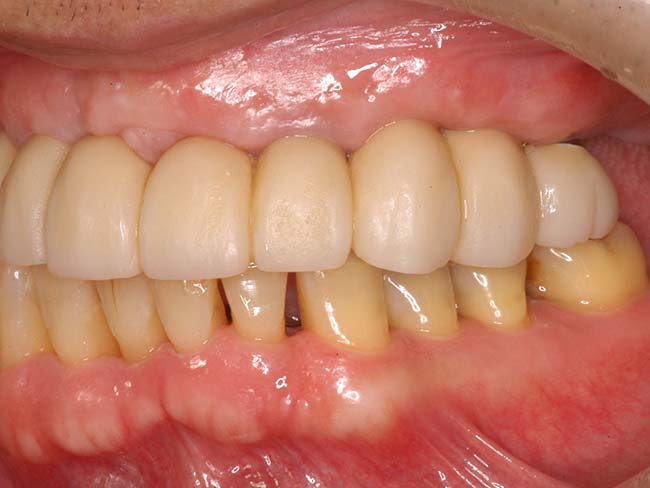

若い歯周病患者(30代)のAll-on-4

| 患者さま情報 | 治療期間 | 治療費 |

|---|---|---|

| 30代 男性 | 1年4ヶ月 | 2,491,000円 |

リスクや副作用

・保険外で高い

・治療が適応とならないケースがある。

・十分なメンテナンスがないと、失敗やトラブルを招く可能性がある。

治療経験・技術がある医師による治療が必要となる。

・外科的治療が必要